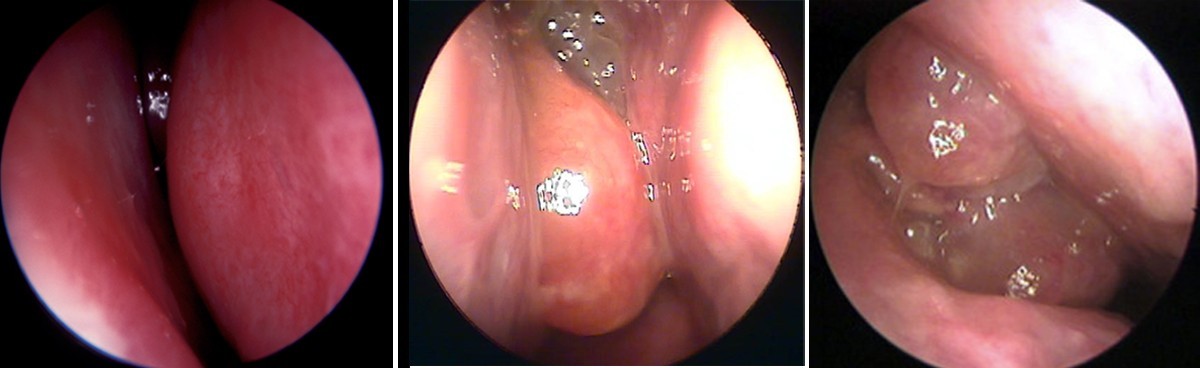

Phù nề niêm mạc mũi gây nghẹt mũi do giãn mạch và sung huyết cuốn mũi

Đặc biệt, cuốn mũi dưới chứa hệ thống xoang tĩnh mạch lớn (venous sinusoids). Khi phản ứng viêm xảy ra, các xoang này giãn ra nhanh chóng, làm đường thở hẹp lại dù dịch không nhiều.

Nghẹt mũi làm tăng áp lực xoang gây đau đầu vùng trán và sau hốc mắt